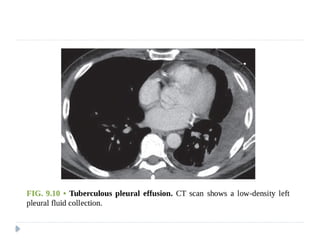

 Tuberculous exudate is distinguished by its high

lymphocyte content.